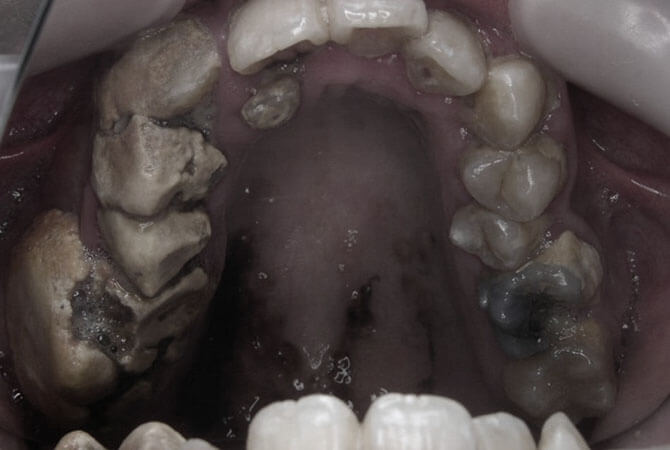

顎骨骨炎